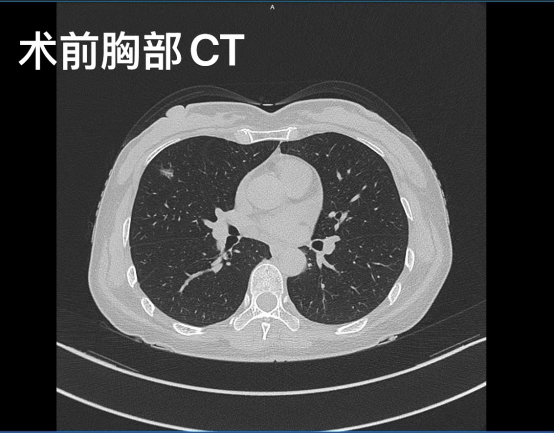

2025年3月,50 歲的李女士因?yàn)槿榉棵浲辞巴以喝橄偌膊≈行年悵嵔淌陂T診就診,經(jīng)乳腺彩超和活檢確診為右乳浸潤性癌。在乳腺癌術(shù)前評估過程中,胸部CT檢查發(fā)現(xiàn)李女士右肺中葉實(shí)性結(jié)節(jié),經(jīng)胸外科會(huì)診考慮原發(fā)性肺癌。

為了給李女士制定更具有針對性和個(gè)體化的治療方案,乳腺疾病中心聯(lián)合胸外科多次組織多學(xué)科聯(lián)合會(huì)診,仔細(xì)分析病情、閱讀影像圖像、設(shè)計(jì)多種手術(shù)方式及可能的手術(shù)入路。針對李女士年齡較輕,對美容要求較高,多次表達(dá)希望一次手術(shù)完整切除兩個(gè)癌灶的期望,胸外科蒲強(qiáng)教授和陳潔教授討論決定,將“單孔VATS腔鏡肺癌手術(shù)”及“單孔腔鏡保乳手術(shù)”結(jié)合,創(chuàng)新性地通過一次手術(shù)完成病灶切除。